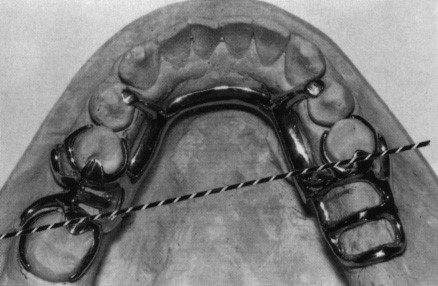

- Có yêu cầu vật giữ gián tiếp bổ sung ngoài các vật giữ trực tiếp không?

Trong nhiều trường hợp, móc có thể đóng vai trò là vật giữ trực tiếp và gián tiếp (Hình 3.1.12).

Dựa trên phân loại Kennedy, người ta có thể xác định xem có cần vật giữ gián tiếp bổ sung hay không. Nếu cần vật giữ gián tiếp thì nó sẽ nằm vuông góc với trục xoay (đường điểm tựa).

Đường điểm tựa được xác định bởi một đường được vẽ nối các tựa mặt nhai ở phía sau nhất của hàm khung.